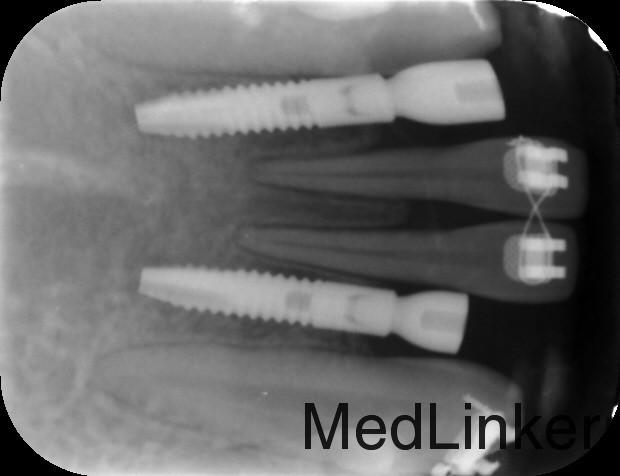

治疗:1、联合正畸科治疗,正畸科移动双侧中切牙至中线两侧后留出位置行种植治疗 2、常规消毒铺巾局部麻醉,切开翻瓣,植入Astra种植体3.0*8mm种植体两枚,严密缝合

多学科联合治疗是未来的趋势,这个病例患者先天缺牙,且间隙大,可先做正畸治疗腾出缺牙空间行种植治疗,种植治疗后已高基台保持间隙